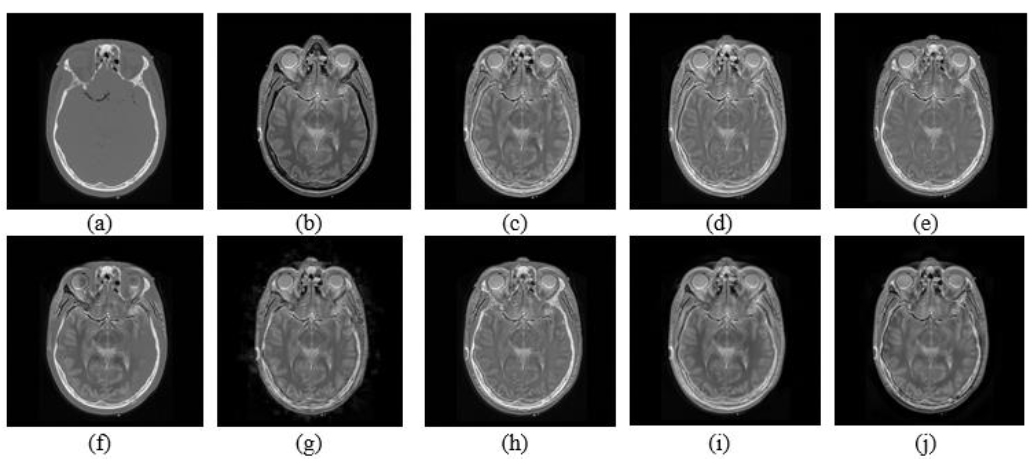

Basic methodology of CT and MRI fusion in the transform domain described along with CT and MRI images from AANLIB [19].